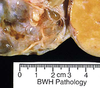

fibroadenoma

31

fibroadenoma

32

fibroadenoma

33

fibroadenoma